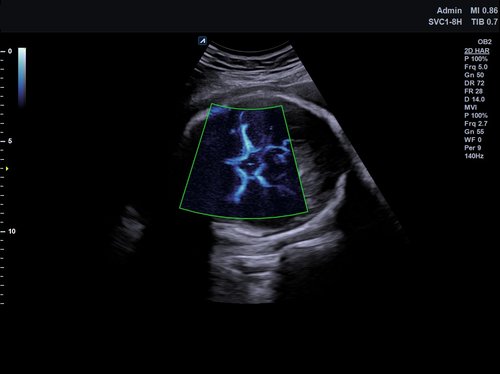

Das X-CUBE 70 bietet modernste Technologien für eine objektive und akkurate Diagnose. Intelligente klinische Module heben das System auf ein neues diagnostisches Niveau. Es erweitert Ihre Fähigkeiten und die Bandbreite Ihrer Möglichkeiten. Dazu gehören Module wie MicroView, point Shear Wave Elastographie (pSWE), oder auch die Kontrastmittelsonographie.

• SVC1-8H (1-8 MHz) für Ultraschalluntersuchungen in Bereichen Abdomen, Geburtshilfe, Gynäkologie, Urologie, Pädiatrie, EM